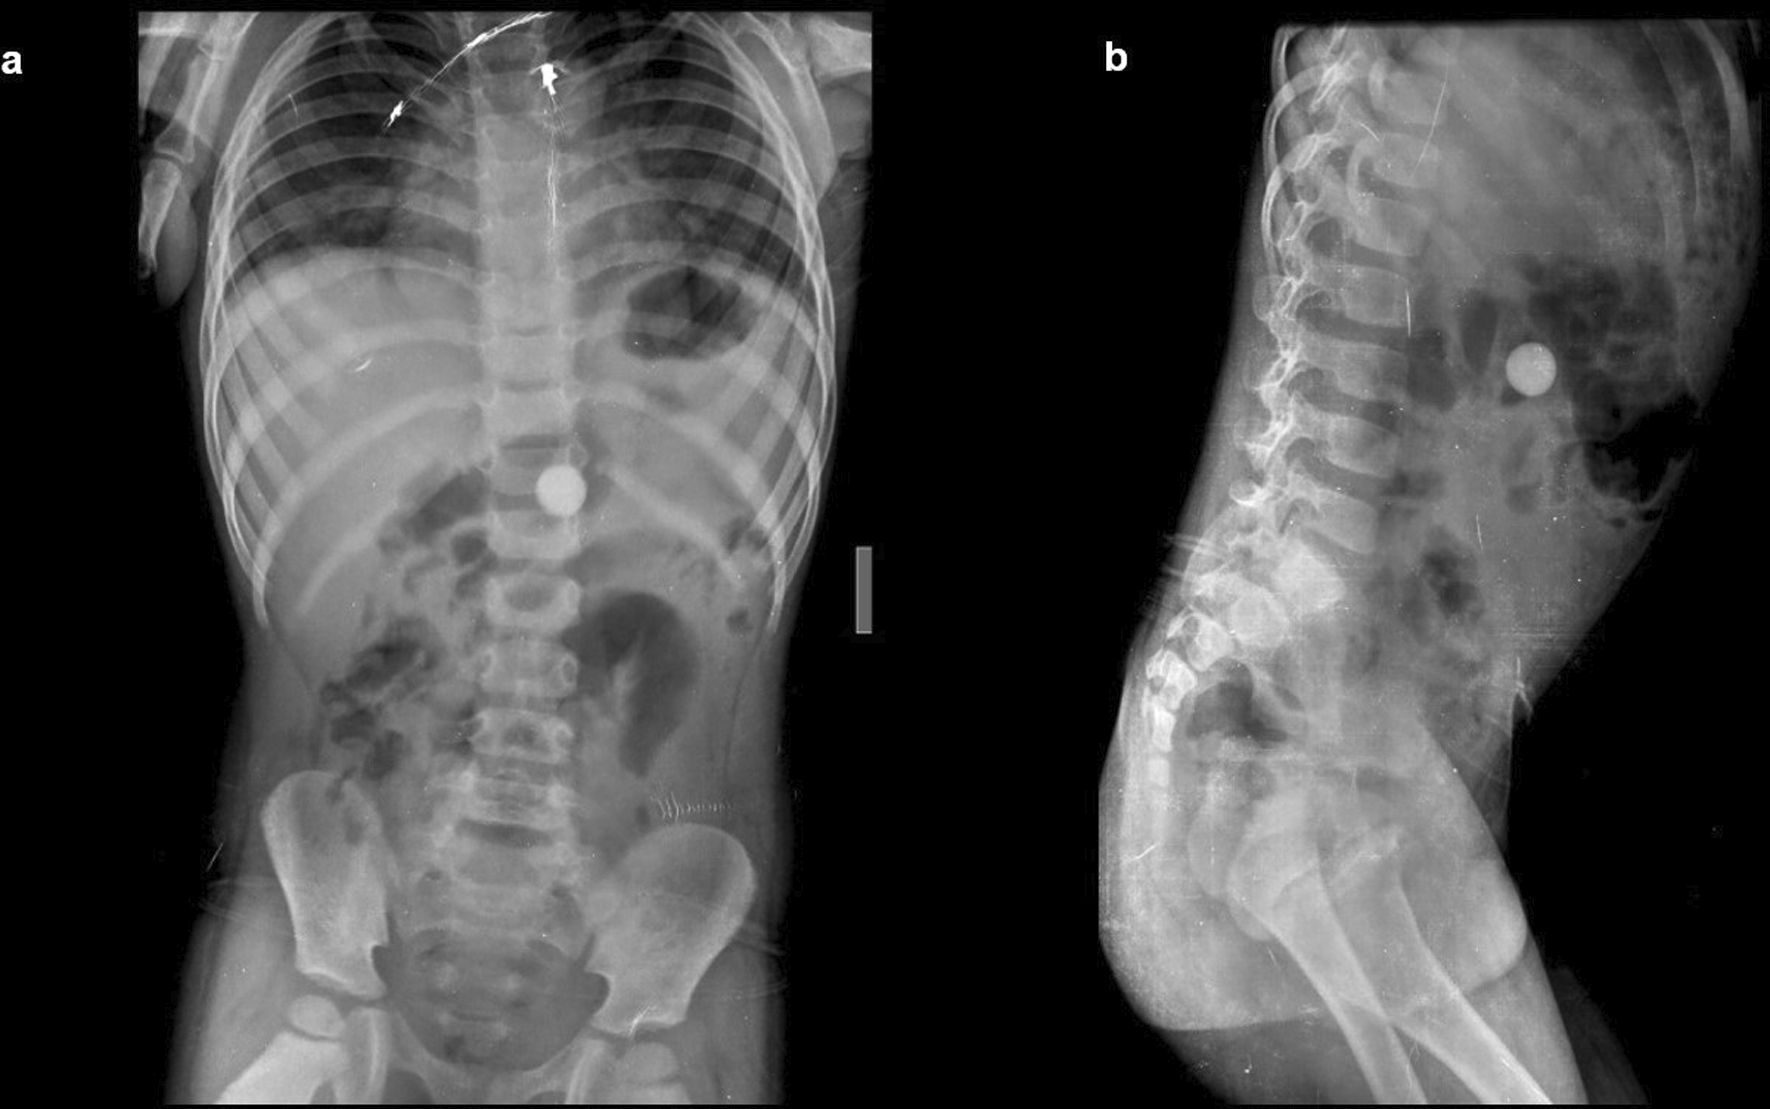

Case 1: A four-year-old child came with a history of abdominal pain. On a radiograph of the abdomen, frontal and lateral projections reveal circular radio opacity on the left side at the level of the L2-L3 disc suggestive of coin, which the patient had accidentally ingested. It passed through the gastro-intestinal tract without a problem.

Case 2: A 34-year-old male carpenter by profession accidentally ingested a screw. A radiograph of the abdomen in frontal and lateral views reveals a nail at the level of the L4 and L5 vertebrae in the gastrointestinal tract, which passed without any problems.

The swallowing of foreign bodies is a common condition in children and mentally challenged individuals.3–5 Fortunately, most ingested objects move through the digestive system without causing any problems (Figure 1a,b). Sharp and elongated objects can pass uneventfully (Figure 2a,b); however, they can pierce the mucosal lining and seriously damage or completely perforate the intestinal wall (Figure 3a-e). The object may just partially puncture the gut wall, resulting in a chronic inflammatory condition with few symptoms that is diagnosed months or years later.5–7